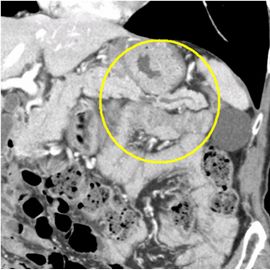

CT検査にて膵体部より末梢の主膵管拡張を認め、精査の結果、膵体部腫瘍疑いと診断した。腹腔鏡補助下にて膵体尾部切除術を施行した。病理診断結果は上皮内膵がん(Pan-In 膵がん)であった。

CT画像